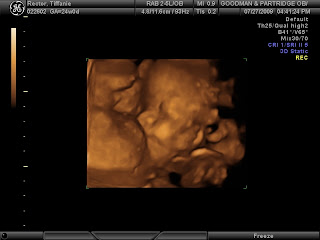

We had another ultrasound yesterday (7/27/09). We are at 24 weeks and just pushing right along. The ultrasound tech confirmed that Bethanie really is a girl because Bryan still wasn't believing it...but it's for sure! Her legs are extremely long and everything is still going great. Four chambers in the heart, beating beautifully...153 bpm. She weighs 1 pound 10 ounces right now. She's nice and healthy and happy...she was being shy yesterday. First she was trying to hide behind her arm...and then she was smooshing her face up against the placenta, guess she was too tired to be modeling. She had a long day yesterday jumping on her trampoline (my bladder). Haha. Anyway...everything's going well, so here are her 24 week ultrasound pictures. ENJOY!!